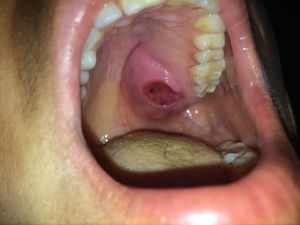

age 40 yrs.. female patnt..unaware of swellng from last 2 mnths.. no pain and no sensation..

it is present on palate and second molar area and this tooth is also mobile

i thnk it is mucoepidermoid carcinoma... bcz duration is only 2 mnths.. ulceration.. nd there is no sensation at that area

It might be tertiary syphilis judging by the aspect and the fact it doesn't hurt.

Mucocoele is painless but mostly present in the lower lip,epulis is painfull present in b/w teeth on gums.......this cant be either.π.

i think it is either syphilitic lesion or a premalignant lesion which will progress to mucoepidermoid carcinoma..